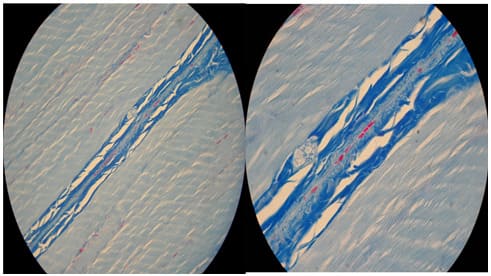

It is also clear that the tendinous system (tendons, endomysium and perimysium) is a continuous structure with no junctions. It is important to notice that the tendinous system is the structure that tears first in stretch-type injuries therefore one should follow the tendinous system to detect a tear. Ultrasound is a method of choice in this type of diagnostics. It only takes some effort to learn all the muscles tendinous systems anatomy. The end (cone) of the myofiber shows interesting feature of the tendinous system. At the level of the cone longitudinal striations can be seen on longitudinal/oblique sections (Figures 8,9,10). This phenomenon can be explained in only one way. This is where the loose connective tissue covering the whole myofiber must compress to single fibers of compact connective tissue and further on the tendon. It looks as they compress forming thin bands of tendon which gradually become a solid tendon. Therefore the end of the myofiber (the cone) is a transition zone from loose to compact connective tissue. At the cone level despite the parietal myotendinous junction there is another myotendinous junction mechanism. Actin filaments are anchored from one side to the Z-membrane, from the other side instead of interlacing with miosin penetrate through sarkolemma to the extracelular matrix just like integrines - also a parietal MTJ. Transverse sections of the muscle show that bands of endomysium are every few myofibers strengthened by bands of perimysium (Figures 11,12).

On Figures 13,14,15 examples of Azan stained specimens showing what perimysium does to the muscle’s tendinous system structure. During the process of contraction myofiber ripples as do many worms (Figure 16). The difference between a worm and the myofiber is that the worm contracts and relaxes its segments to crawl and the myofiber contracts at the whole length to shorten and bring the origin to insertion generating movement or create a desired position. It is worthy to notice that according to Gray’s anatomy [3] a human sarcomere is approx. 2 mm long in the relaxed state (1mm=1x10-6m=1x10-3mm). That means that a human myofiber has 500 levels of PMTJ for every milimeter of its length. An interesting feature of a myofiber is that the only myofibrills that transmit force directly onto endomysium (that is forming a PMTJ) are those which are peripheral. All other myofibrils transmit their force onto PMTJ indirectly through neighboring myofibrils and at the ends (the cone) of the myofiber. At the cone of myofiber all four types of nerve endings are seen: Ruffini and Vater-Paccini corpuscules, Golgi apparatus and free nerve endings [4] This fact proves that the cone is a key proprioceptive zone of the myofiber.

The whole tendinous system can be clearly visualized by ultrasound. The tendons as well as perimysium+endomysium show in a relaxed muscle as hyperechogenic lines of different thickness. Skeletal muscles show 0,1-0,4mm of anechoic space between the bright lines and that is 4 to16 myofibers (depending of the size of myofibers) per dark space between the lines of endomysium + perimysium in a relaxed state, neutral position. Figures 17,18,19 show the US images of selected muscles.